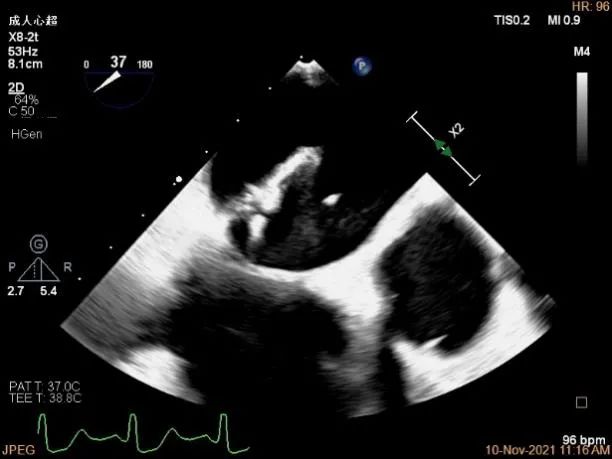

X-plane:下夹子尝试捕获2区脱垂瓣叶

3D证实夹子外侧残余脱垂及瓣叶裂空